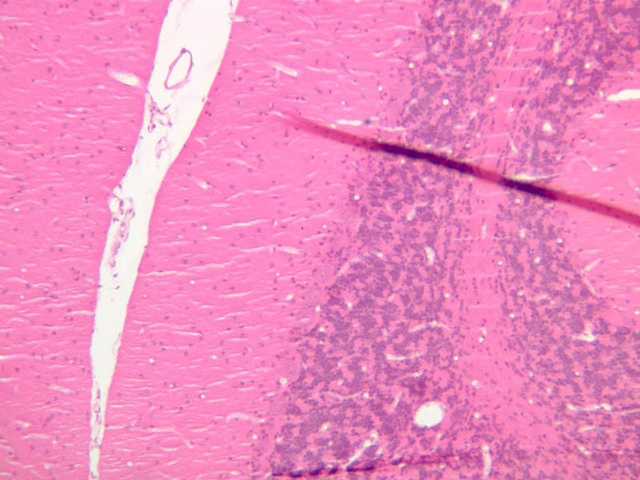

The basic structure of neurons in the CNS is not very different from that of neurons in the PNS, such as the DRGs. The cytoplasm of neurons contains granular basic material referred to as Nissl bodies. These clumps are masses of rough endoplasmic reticulum (RER). A large golgi apparatus is present as well. Nissl bodies stain adequately with H&E and even better with cresyl violet (CV), a stain for RNA and DNA. On the following slides look in the gray matter and find the motor neurons that reside in the ventral gray matter. Then look in the white matter to find the macroglial cells of the CNS, astrocytes and oligodendrocytes.

Examine the sections on slide A-85 with the unaided eye. Find the gray matter located within the interior of the cord (it has a "butterfly" shape). Examine the cresyl violet (CV) stained section first (the bluer one). Find the ventral horn under the microscope and locate the cell bodies of the large motor neurons (A-85, CV [1x] [2.5x-labeled, 10x, 20x, 40x] [2.5x, 10x, 20x, 40x-labeled]; H&E [1x] [2.5x-labeled, 10x, 20x, 40x-labeled]). Motor neurons are among the largest cells in the nervous system, particularly when their long processes are considered. Once again, note the large nucleus, the prominent nucleolus, and the clumps of darkly stained Nissl bodies. Look for neuronal processes – these will not be stained well with the cresyl violet stain (what does this tell you?). Dendrites are numerous and exit the cell as thick trunks that branch extensively. The axon hillock may also be seen as a thick trunk exiting the cell body, but this does not contain Nissl bodies as the dendrites do. Next, examine the dorsal horn (CV [2.5x, 10x, 20x, 40x]) and compare it to the ventral horn. Also examine the white matter (CV [2.5x, 10x, 20x, 40x]; H&E [2.5x, 10x, 20x, 40x-labeled]). Axons are more difficult to identify because they exit the soma as thin processes, and the irregular course they take makes them difficult to follow in sections. The term neuropil refers to the complex, felt-like net of axonal, dendritic, and glial arborizations that form the bulk of the gray matter of the CNS and in which the nerve cell bodies are embedded. To appreciate the complex wiring of the CNS, examine slide A-83 (Sevier Ag [2.5x, 10x, 20x, 40x]), which is a section from the brainstem stained using a silver impregnation technique.